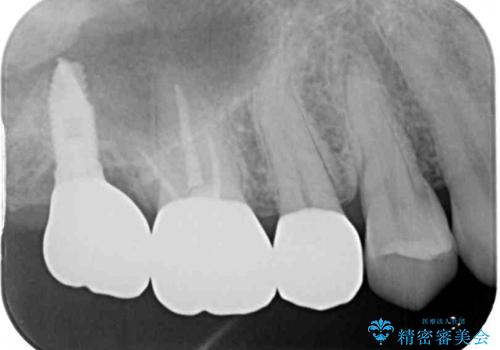

右上の一番奥の歯が欠損しており、その手前の歯2つを土台に連結されたクラウンが装着されていました。

不安定な咬み合わせとなっており、クラウンの表面が剥離していたため、インプラントによる欠損補綴治療を行い、手前2つの歯も一緒に補綴治療を行うこととしました。

治療中の仮歯も頻繁に壊れておりましたが、インプラントの土台が歯肉上に出てからは咬み合わせが安定し、仮歯が壊れることもなくなりました。